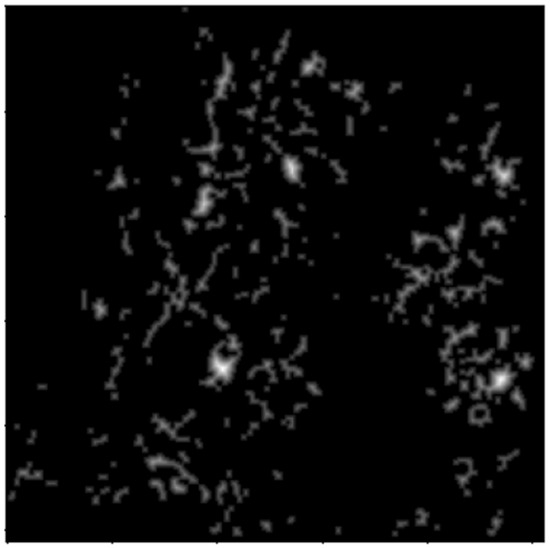

2.2. Image Enhancement

2.2.1. Thresholding